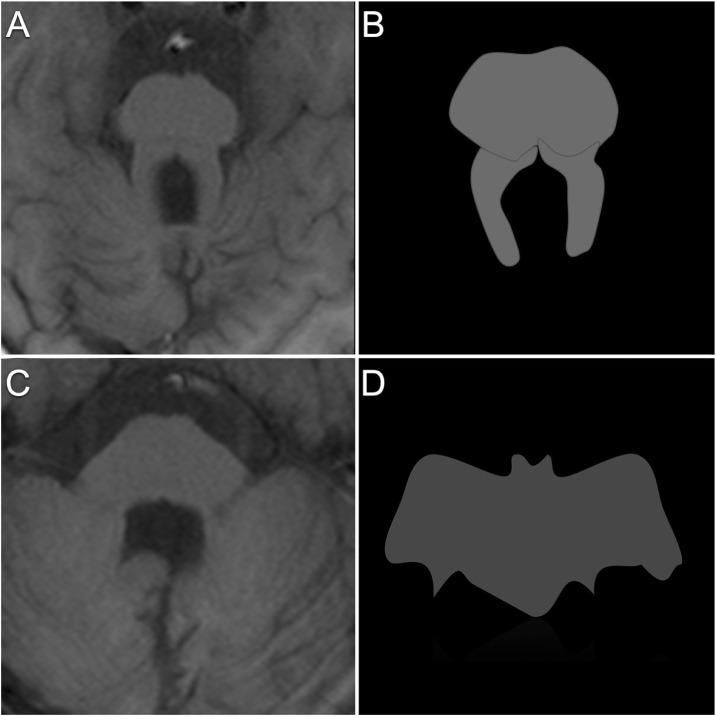

Joubert Syndrome, manifests in a spectrum of neurological symptoms. This case describes a 7-year-old girl with perinatal complications, and subsequent neurodevelopmental challenges. An MRI confirmed the diagnosis of Joubert syndrome, with the distinctive "molar tooth sign" being a key imaging characteristic. Approximately 25% of cases exhibit nephronophthisis, impacting kidney function, further complicating the clinical picture. Diagnosis relies on imaging and management necessitates a multidisciplinary approach, addressing symptoms and complications, with prognosis linked to the presence of organic disease. The case emphasizes the significance of a multidisciplinary strategy, including genetic counseling, and underscores the diverse manifestations of this syndrome. Prenatal identification through ultrasound and MRI plays a crucial role in diagnosing and treating this rare condition.

乔伯特综合征表现为一系列神经症状。本病例描述了一名7岁女孩,有围产期并发症及随后的神经发育挑战。磁共振成像(MRI)确诊为乔伯特综合征,其独特的“磨牙征”是关键的影像学特征。约25%的病例出现肾单位肾痨,影响肾功能,使临床情况更加复杂。诊断依靠影像学检查,治疗需要多学科方法,处理症状和并发症,预后与器质性疾病的存在有关。该病例强调了包括遗传咨询在内的多学科策略的重要性,并突出了该综合征的多样表现。通过超声和MRI进行产前识别在诊断和治疗这种罕见疾病中起着关键作用。